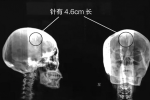

安徽淮北一名女子脑里藏针46年:淮北刘女士,今年48岁,因为头疼在医院检查,医生在她左侧颅脑里发现了一枚针,针长约4.6cm,直直地插在她的脑袋里。医生推测,这枚针在刘女士的脑子起码